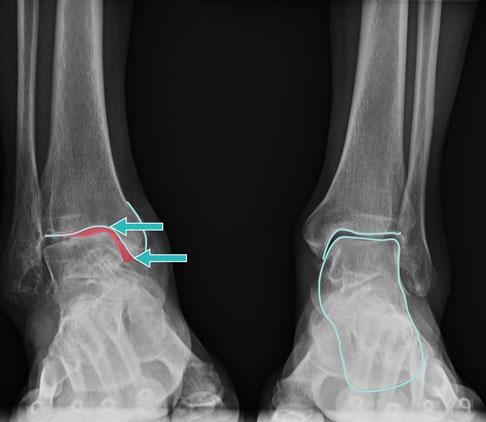

Nicht nur die Form der Sprunggelenksarthrose spielt für die Prothesenversorgung eine wesentliche Rolle, die Versorgungssicherheit ist auch von der Art und Lage der Arthrose im oberen Sprunggelenk (OSG) abhängig.

- konzentrische Arthrose: gleichmäßige Abnutzung des Gelenkknorpels bei korrekter Stellung des Sprungbeins (Talus)

- asymmetrische (exzentrische) Arthrose bei Fehlstellung des Sprungbeins (Talus) durch Verschiebung nach vorn und hinten oder Rotationen

- Varusarthrose bei nach außen gekipptem Sprunggelenk

- Valgusarthrose bei nach innen gekipptem Sprunggelenk